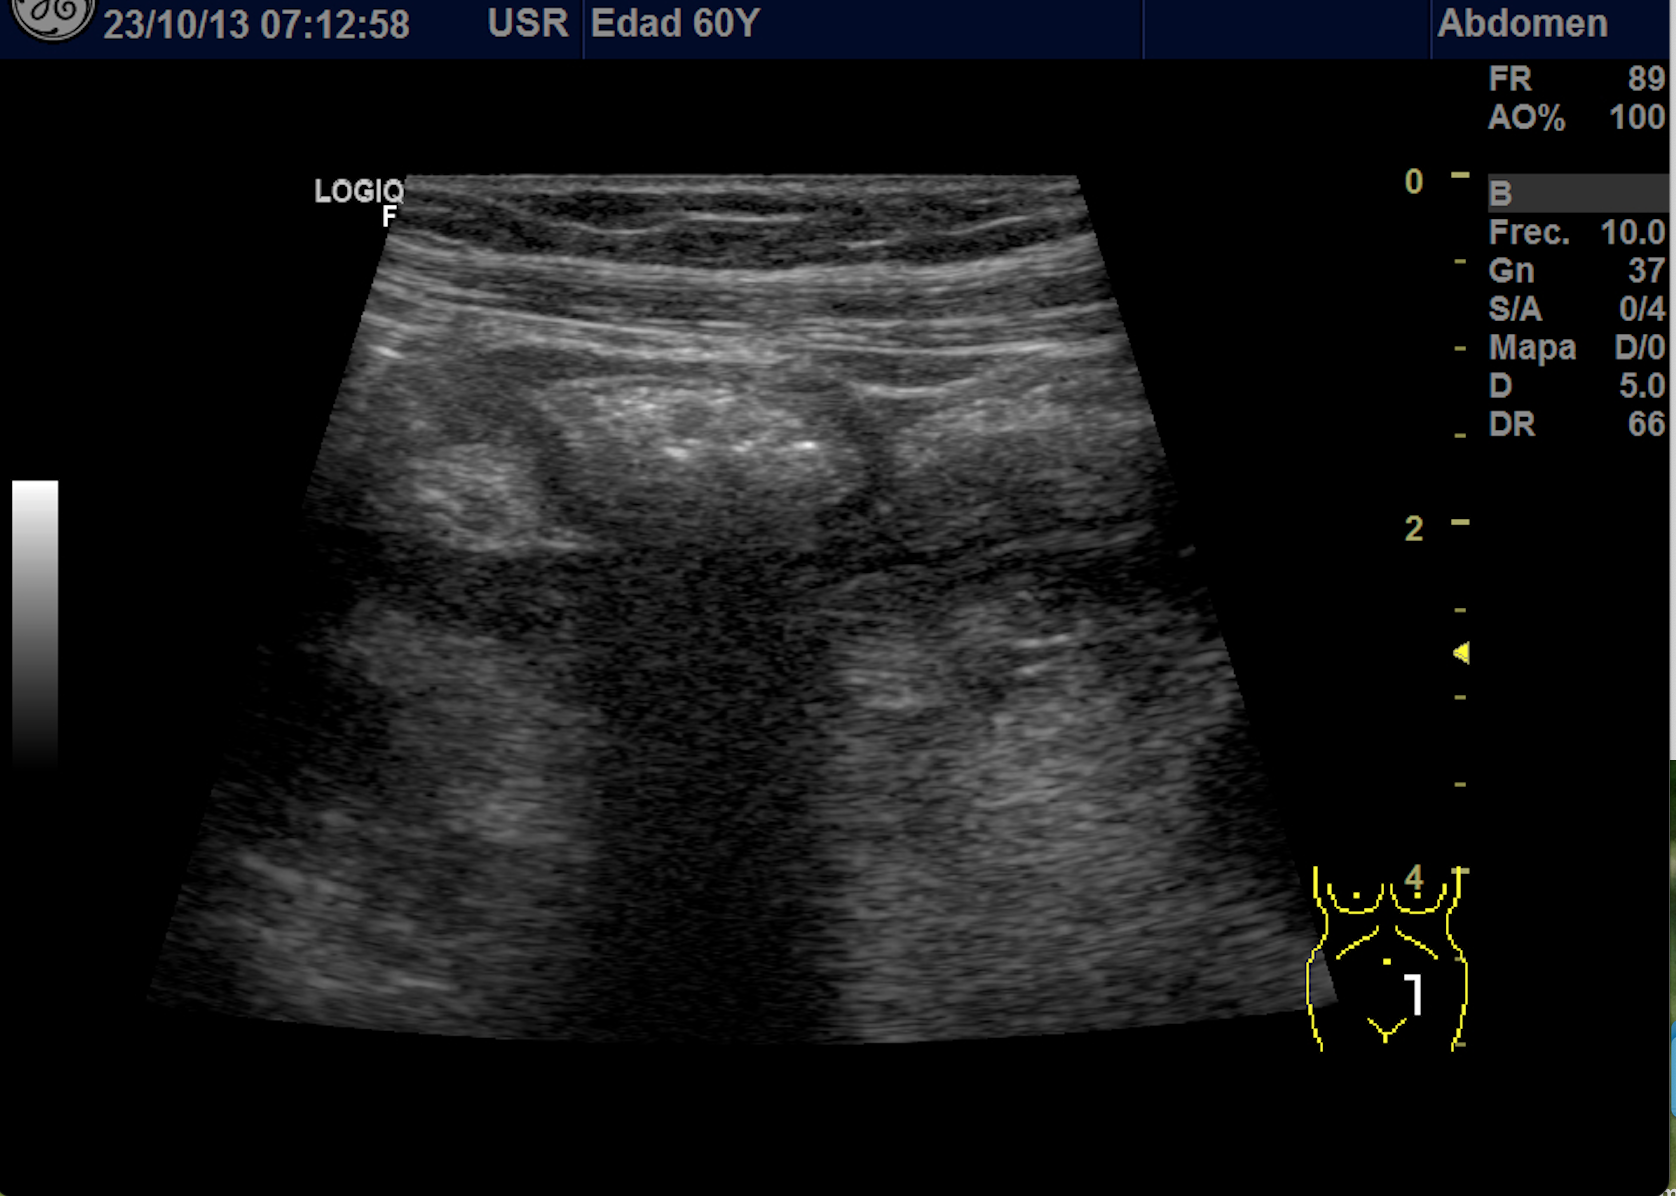

También se realiza ecografia en urgencias del hospital.

En el hospital se realiza una nueva ecografía en el servicio de radiología confirmando el diagnóstico de sospecha: diverticulitis aguda en sigma distal sin datos de complicación. Hinchey 1A.